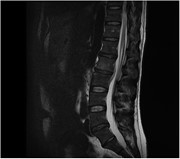

Lumbar spine osteomyelitis and epidural abscess formation secondary to acupuncture

Vinesh Godhania

Journal of Surgical Case Reports, Volume 2016, Issue 3, March 2016, rjw035, https://doi.org/10.1093/jscr/rjw035